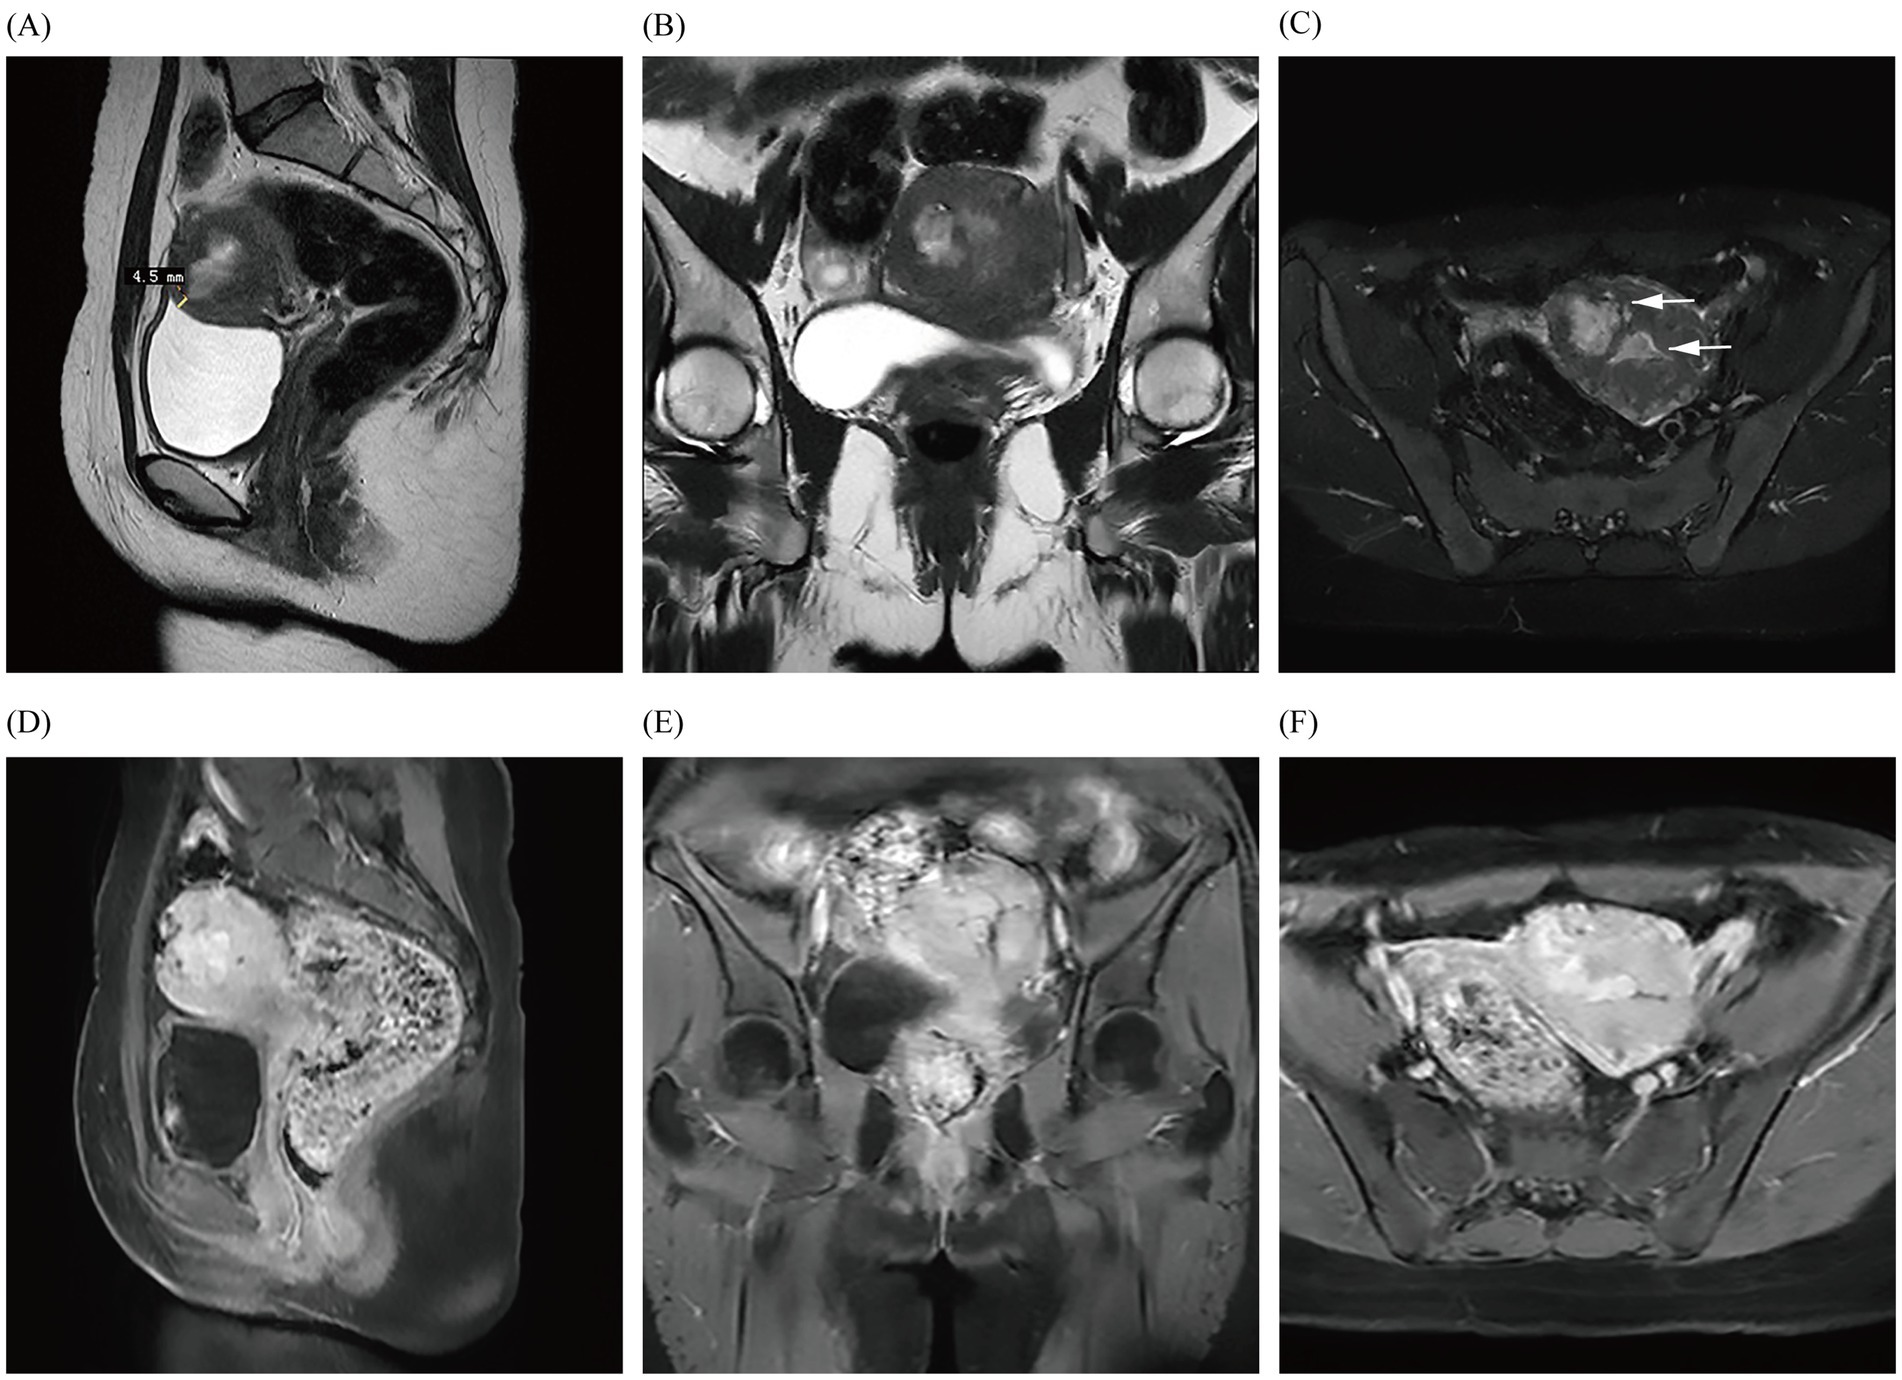

Figure 2

Images (A–F) show the MRI in January 2023, demonstrating a fibroid with just under a 50% submucosal component (arrows) that is closest to the uterine serosa layer by approximately 4.5 mm; they also reveal obvious enhancement of the fibroid.

In our case, the young patient had no history of cesarean section or congenital malformations of the uterus, used a Mirena IUD within its expiration date, and showed a history of hysterectomy for uterine fibroids within three generations of her mother. In 2001, De Iaco et al. reported a case in which transcatheter embolization of uterine arteries caused localized tissue necrosis and ischemic contraction of the uterine myometrium postoperatively, and they observed a full-thickness discontinuity of the uterine wall in the location of previous hysteroscopically directed submucosal myomas, as detected through hysteroscopy (7). In one case, the patient’s pelvic MRI enhancement before hysteroscopy suggested localized thinning of the anterior wall of the uterus, with the thinnest area measuring at only 4.5 mm. However, the enhancement of ≥80% of the scar area indicated that the blood flow in the scar area of the uterine myometrium was equivalent to the flow in normal tissues (5). The potential mechanism for the uteropelvic fistulae found in the patient was also similar to the mechanism underlying fistula formation after uterine artery embolization. In January 2023, dynamic pelvic MRI revealed that the submucosal myoma was located approximately 4.5 mm from the uterine serosa. During the subsequent hysteroscopic myomectomy, the excised leiomyoma was found to penetrate deeply into the surface of the uterine serosa, and the heat of the electrocautery of the uterine leiomyomas damaged or decreased the elasticity of the muscle wall; these conditions may have led to a weakened area, posing a risk factor for the formation of uterine fistulae. Subsequently, recurrent submucosal myomas can easily grow through this weakened area into the pelvic cavity. The patient’s symptoms were not severe, likely due to the lack of menstrual blood flow into the pelvic cavity.